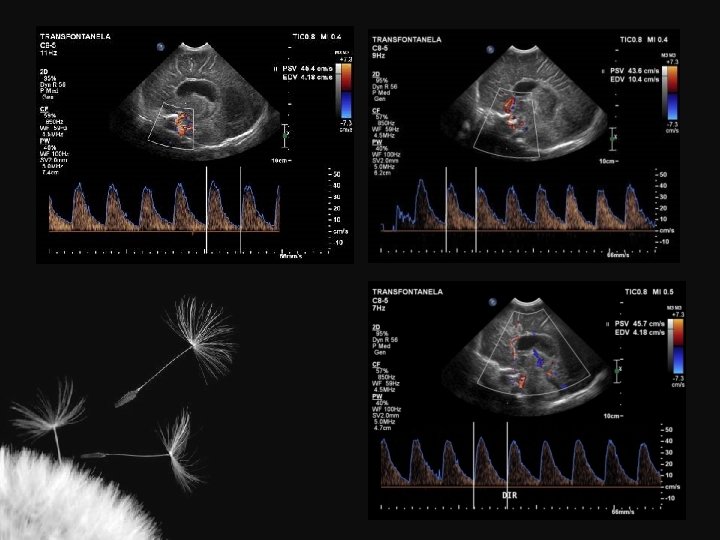

Artérias cerebrais normais

Valores normais ACI ACA AB Vs (cm/s) 50 + 15 42 + 15 41 + 16 Vd (cm/s) 11 + 4 11 + 5 11 + 4 TAMX (cm/s) 22 + 6 21 + 9 19 + 7 0, 77 + 0, 08 0, 73 + 0, 08 0, 72 + 0, 09 RI Deeg KH. Neuroradiology 32: 60 -63

Índice de resistência (IR) nas artérias intracranianas ACA ACI Martin (1982) 0, 75 + 0, 03 Jorch (1986) 0, 74 + 0, 06 Lipman et al. (1982) 0, 79 + 0, 04 Perlman et al. (1985) 0, 66 + 0, 06 Deeg (1989) 0, 73 + 0, 08 AB 0, 77 + 0, 07 0, 73 + 0, 06 0, 77 + 0, 08 0, 72 + 0, 09 ACA artéria cerebral anterior, ACI artéria carótida interna, AB artéria basilar IR pré-termo 0, 79 + 0, 02 IR > 2 anos 0, 50 + 0, 08

Considerações IR = S – D S Perfusão Q = A x TAV Aumento da PIC 1. Aumento da velocidade sistólica 2. Diminuição da velocidade diastólica Compressão fontanelar 1. Normal – aumenta até 6% 2. Diminuição da complacência craniana – > = 20%